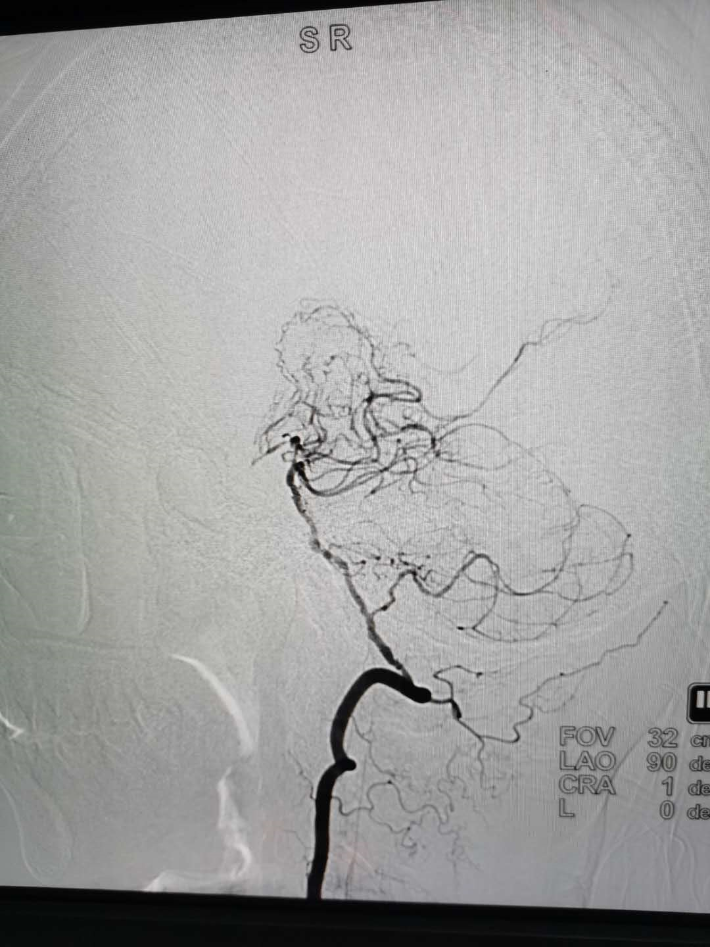

2020.04.24日局麻下行全脑血管造影,弓上造影显示弓上血管发育异常,双侧颈总动脉共干,双侧椎动脉分别起始于双侧锁骨下动脉,右侧颈总动脉及颈内动脉分叉处重度狭窄,狭窄率≥95%,右侧椎动脉造影显示基底动脉显影良好,并且通过右侧后交通动脉代偿右侧大脑半球,考虑手术风险较大,与家属充分沟通后,终止手术。

从以上分析:患者有一定的手术适应症,但通过DSA造影发现右侧大脑中动脉已闭塞,即使行支架植入术患者获益不大,且存在高灌注风险;患者DSA造影显示弓上血管发育异常,双侧颈总动脉共干,双侧椎动脉分别起始于双侧锁骨下动脉,右侧迷走锁骨下动脉,手术有一定难度; 虽然患者右侧大脑中动脉已闭塞,但无明显肢体瘫痪,侧枝循环已建立,考虑慢性闭塞可能性大,开通后获益不大,但存在较大风险,手术弊大于利,建议保守治疗。

如果手术开通,有可能闭塞右侧颈外动脉,导致右侧大脑中动脉存在的侧枝循环发生障碍,导致患者症状加重; 患者从外院CTA结果看,存在后交通动脉、前交通动脉,即使颈内动脉完全性闭塞,右侧大脑前动脉仍有血供; 如果手术开通颈内动脉,大量的血流可能导致右侧中动脉建立的纹状血管高灌注,出现出血等灾难性后果。